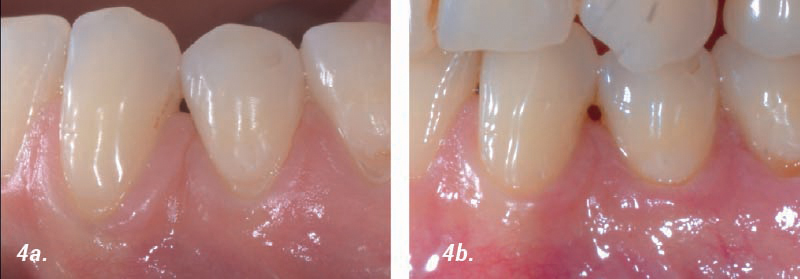

Cobertura de recesión múltiple

Caso aportado por el Dr. Thomas Pierchalla, Muenster, Alemania:

• 4a. 9 meses de postoperatorio.

• 4b. 9 meses de postoperatorio.

• 5a. Ganancia de volumen del tejido blando 9 meses después de la operación frente a situación inicial.

• 5b. Corte transversal después de 9 meses del postoperatorio versus margen creado.